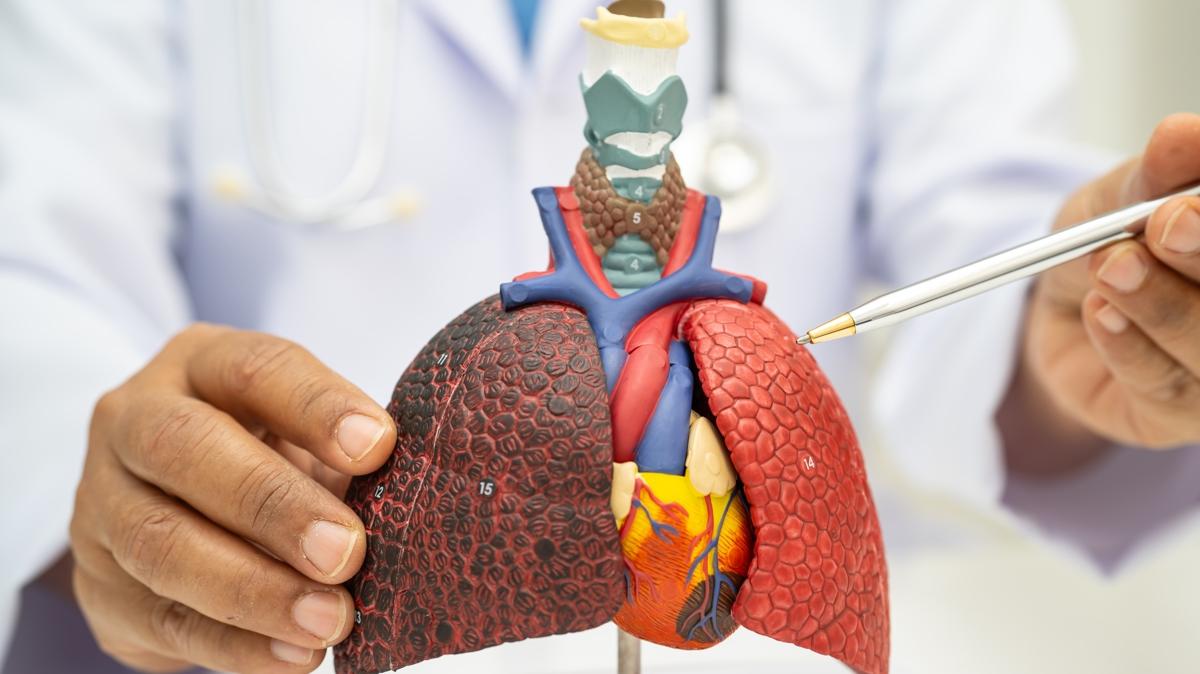

Akciğerdeki nodüller kırmızı alarm işareti olabilir. Kişideki akciğer nodülünün büyüklüğüne göre kanser olma ihtimalinin arttığını söyleyen Göğüs Hastalıkları Uzmanı Dr. Aziz Uluışık, "İyi huylu nodüllerde gereksiz cerrahi girişimden kaçınmak gerekir. Kötü huylu nodüllerde ise erken dönemde tanı konarak ameliyatla sağ kalım süresi artırabilir." dedi.

Günümüzde bilgisayarlı tomografi cihazlarının gelişmesiyle akciğerlerdeki nodülleri saptamanın kolaylaştığını ifade eden Uzm. Dr. Aziz Uluışık, şöyle devam etti:

"Kötü huylu (malign) nodüllere mümkün olduğunca erken dönemde tanı konulup ameliyat edilmesi halinde sağ kalım süresi artar. İyi (benign) nodüllerde ise gereksiz cerrahi girişimden ve buna bağlı oluşacak sorunlardan kaçınmak gerekir. Bu nedenle nodül saptandığında nasıl bir karar verileceği çok önemlidir. Günümüzde bilgisayarlı tomografi (BT) cihazlarının gelişmesi ve tomografi çekilen hasta sayısı artması sayesinde akciğerlerdeki nodülleri saptamak kolaylaştı. Akciğer tomografilerinin yaklaşık yüzde 30'unda bir veya birden fazla nodül saptama ihtimali vardır. Ancak bunların önemli mi, önemsiz mi, kötü mü yoksa iyi huylu mu olduğuna karar vermek bazı durumlarda zor olabiliyor."

NODÜLÜN BOYUTU ÖNEMLİ

Uzm. Dr. Aziz Uluışık, öncelikle görülen nodülün boyutunun çok önemli olduğunun altını çizerek, şu şekilde konuştu:

"3 mm ve daha küçük nodüllerin kansere bağlı olma ihtimali yaklaşık yüzde 0,2 gibi düşük bir orandadır. 8-20 mm arasındakilerde bu ihtimal yüzde 18'e çıkarken, 20 mm'den büyük nodüllerde yüzde 64'den fazladır. Saptanan bir nodülün takibinde eski tomografiler ile karşılaştırmak önemlidir. Nodül boyutunda yüzde 25'den fazla bir artış olması kanser riskinin yüksek olduğuna işaret eder. Boyutundan sonra nodülün kenarlarının düzgün olup olmadığına bakmak gerekir. Kenarı düzensiz olan nodüllerin kanser riski 5 kat fazladır. Nodülün içinde kireçlenme bulunması, çoğunlukla iyi huylu olduğu anlamına gelir. Genellikle 2-3 yıl, bazı durumlarda ise 5 yıllık izlemde eğer nodülde bir değişiklik yoksa ileri incelemeye gerek yoktur."

KANSER RİSKİ NODÜL ÖZELLİKLERİNE GÖRE TAYİN EDİLEBİLİR

Akciğer grafisinde ya da tomografide büyüme saptanan her nodül olgusunda sakıncalı bir durum (kontrendikasyon) yoksa doku tanısının elde edilmesi gerektiğini söyleyen Uluışık, kanser ihtimali yüksek nodüller için şunları söyledi:

"Büyüme saptanan her nodülde kanser ihtimali arttığı için radyolojik veya cerrahi biyopsi gerekir. Kanser ihtimali yüksek nodül varlığı ve riskli hastalarda ameliyat ile nodülü çıkarmak hayat kurtarıcı olabilir. Sigara kullanmış ya da halen kullanmakta olan, 40 yaş üzeri ve de kendisinde ve 1. derecede akrabalarında kanser öyküsü bulunan kişiler yüksek risk grubuna girer. Özellikle ileri yaş ve içilen sigara miktarının çokluğu ile kanser potansiyeli artar. Hekim görülen nodülün özelliklerine bakarak kanser riskini tayin eder. Buna göre de hastanın tomografi ile takip edilmesi mi, yoksa biyopsiye mi gönderilmesi gerektiğine karar verir. Bu karar hasta adına hayati olabilir. Her hasta ve nodül için aynı senaryo geçerli olmayabilir. Bu yüzden sayılan özelliklerin sadece ihtimal üzerinden değerlendirildiği ve her zaman için düşük ihtimalli durumlarla da karşılaşılabileceği unutulmamalıdır."